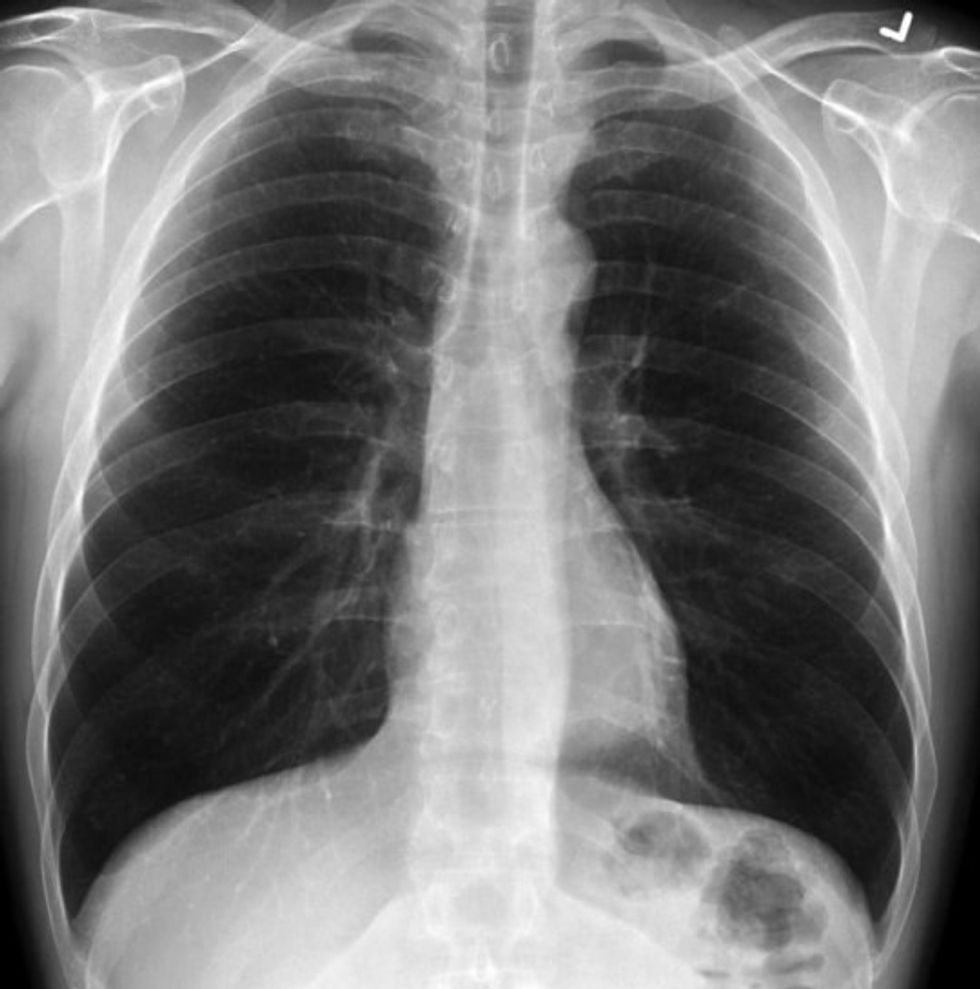

Ndërsa u shfaq në CBS DFW, mjeku ndau tre imazhe të rrezeve X: një nga një pacient i shëndetshëm, një nga një duhanpirës dhe një tjetër nga një pacient me COVID-19. /Telegrafi/

Në anën tjetër, mushkëritë e duhanpirësve janë më të mjegullt dhe tregojnë më pak dëme, madje edhe në mesin e atyre që kanë pirë duhan për vite, tha Dr Bankhead-Kendall.